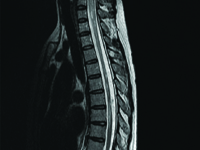

Devic's disease (neuromyelitis optica, NMO) is a chronic demyelinating disease of the central nervous system primarily damaging the spinal cord and optic nerves. Formerly considered a variant of multiple sclerosis multiple sclerosis, NMO is now classified as a separate disease entity with a specific pathogenesis related to associated with reactivity against aquaporin 4.

Arachnoid calcifications coexisting with epidurally located spinal canal lipoma, are a rare cause of spinal cord compression, especially in children.